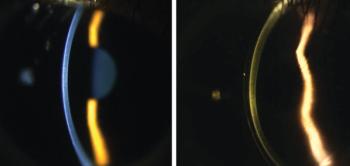

Successful outcomes demand both corneal and contact lens expertise.